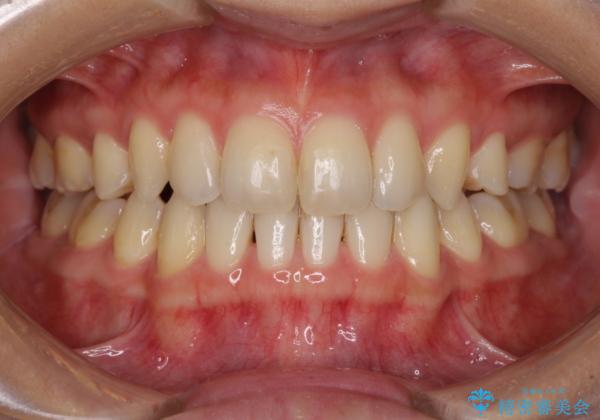

- 以前の矯正治療の後戻りにより、上の前歯にスペースができたことを気にして来院された患者様です。

インビザラインを用いて前歯のスペースを閉じつつ、上下の咬み合わせを構築していくこととしました。

隙間の空いてしまった前歯は、矯正治療で治療を行っても後戻りが起こりやすい傾向にあります。

マウスピースの保定装置をしっかりと装着しても空いてしまうため、細いワイヤーによる保定を併用することで後戻りを防止しています。